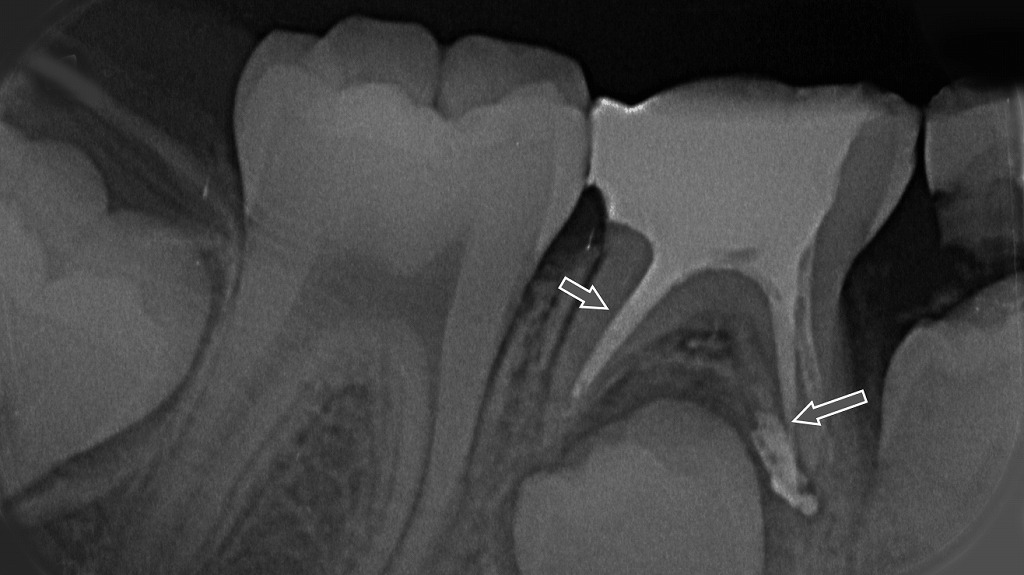

神経治療(乳歯の抜髄)

乳歯の抜髄処置を行ったX線画像。矢印の部分に、感染した神経を取り除いた後の根管と薬剤の充填状態が確認できます。根の先までしっかり清掃・消毒し、炎症の再発を防ぐための治療が行われています。